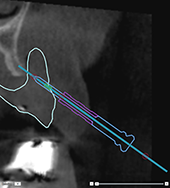

Correct inclination and depth of

anchor pins

To stabilize the surgical

template for implant insertion, anchor pins can be placed at strategic

positions. Their inclination

and depth are crucial.

The anchor pins can

also serve as lip retractors during surgery. Anchor pins spread too widely

within the arch could negatively affect mouth opening. A short-shaft version

of the anchor pin is available to mitigate this effect. Nevertheless,

the anchor pins should be planned so as to offer good access and should

not interfere with the implant sites.